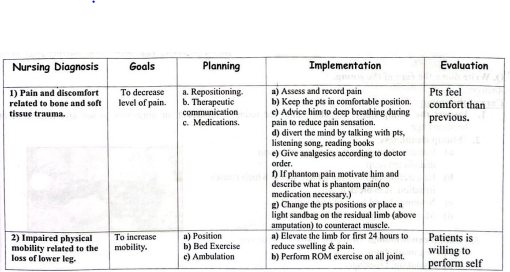

Care of the stump:

1. Inspect the stump daily:

Regular stump for redness, blistering, or abrasions to see any infection, or haemorrhage.

3. Stump conditioning:

The can be done by observing following instructions.

a) Avoid tight bandage.

b) Regular and correct application of a firm elastic bandage.

c) Regular isometric exercise to the stump muscles proximal to the amputation.

d) Repeated messaging to improve the tone of the muscle.

e) Avoiding use of alcohol,because it dries and cracks the skin.

4. Anti-oedema measure:

a. Limb should be elevated with elastropcripe bandage application.

b. All the joint including stump are subjected to active exercise.

c. Stump bandaging is an art and is very useful in preventing the oedema.